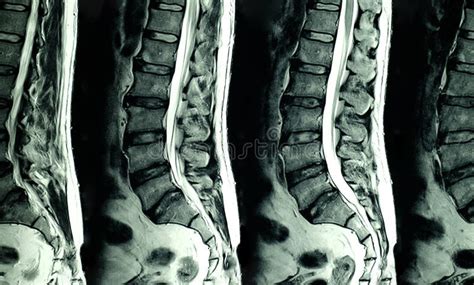

- Risonanza Magnetica (RM): La RM è considerata lo standard di riferimento per la diagnosi di lipomatosi epidurale. Questo esame utilizza campi magnetici e onde radio per creare immagini dettagliate dei tessuti molli, permettendo di visualizzare con elevata precisione l'accumulo di tessuto adiposo nello spazio epidurale e la sua estensione. La RM può anche identificare segni di compressione sul midollo spinale e sulle radici nervose.

- Tomografia Computerizzata (TC): La TC può essere utilizzata come alternativa o in aggiunta alla RM, specialmente se la RM non è disponibile o controindicata. La TC fornisce immagini trasversali dettagliate delle strutture ossee e dei tessuti molli, e può essere utile per valutare l'entità della stenosi del canale spinale.